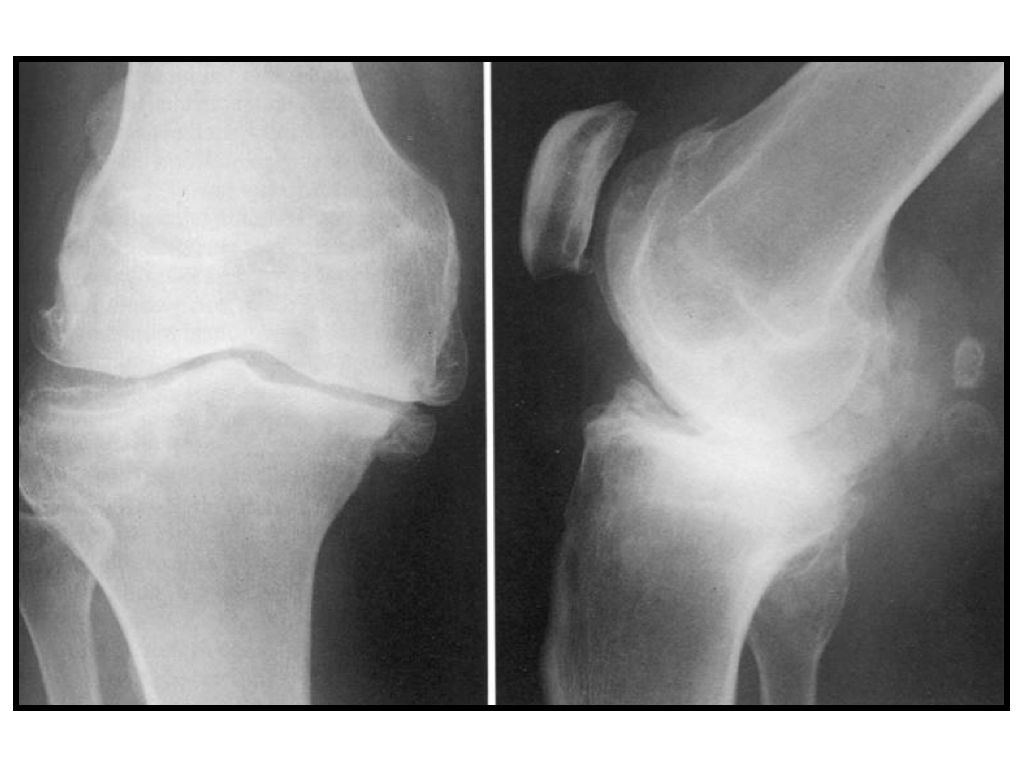

Ist eine Kniearthrose, die sogenannte Gonarthrose, in allen Anteilen des Gelenkes soweit fortgeschritten, dass ein erheblicher Leidensdruck besteht, welchem mit nicht-chirurgischen Mitteln nicht mehr beizukommen ist, dann muss das mechanische Problem des geschädigten Kniegelenkes auch mechanisch gelöst werden.

Beim künstlichen Kniegelenk wird nicht – wie oft fälschlicherweise vermutet – das Knie als Ganzes entnommen und durch ein Scharnier ersetzt, sondern lediglich die geschädigte Gelenkoberfläche ersetzt.

Die geschädigten Oberflächen von Oberschenkel und Unterschenkel werden, jeweils zusammen mit einem dünnen Teil der darunter liegenden Knochensubstanz, entfernt und zur Aufnahme der künstlichen Gelenkoberfläche exakt in Form geschnitten.